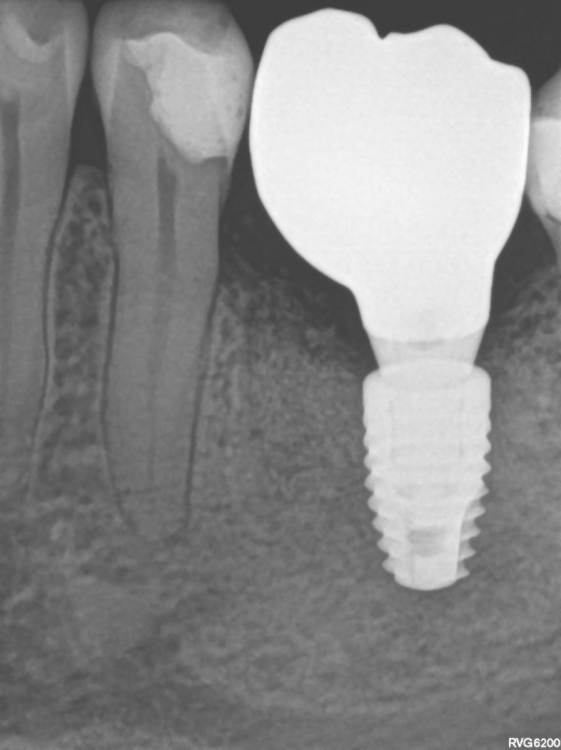

TIGER Опубликовано 22 сентября, 2022 Поделиться Опубликовано 22 сентября, 2022 Всем привет!Давно ничего не закидывал,небольшой клинический случай,банальщина,замещение одиночного моляра,система Straumann понравилась,как всегда только оригинальные компоненты? 8 1 Ссылка на комментарий

Aquarius Опубликовано 23 сентября, 2022 Поделиться Опубликовано 23 сентября, 2022 Красивая работа, спасибо!? Скажите, Вы не помните какой цвет заказывали технику на коронку в области бугров? Как пишете в наряде? Прозрачку, серый, транспарант или просто Д2, к примеру? Никак не могу от своих добиться такого же(( Почти монотон приходит, хоть ты тресни 1 Ссылка на комментарий

TIGER Опубликовано 23 сентября, 2022 Автор Поделиться Опубликовано 23 сентября, 2022 @Aquarius спасибо,я всегда фоткаю с расцветкой и тут мультилэйер циркон 1 Ссылка на комментарий